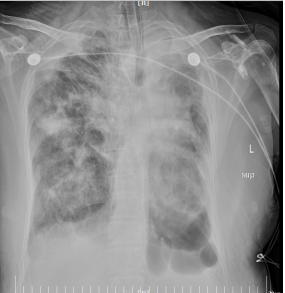

后患者病情持续进展,氧合指数<100mmHg,胸片可见肺部感染进行性加重,SOFA评分13分,“重症肺炎”、“ARDS”、“脓毒血症”诊断明确。

12月14日

复查各项指标示:血常规+超敏C反应蛋白:白细胞数 11.27×10^9/L,中性粒细胞百分比 95.00%,淋巴细胞百分比 2.70%,中性粒细胞计数 10.71×10^9/L,淋巴细胞计数 0.30×10^9/L,血红蛋白浓度 164.00g/L,超敏C反应蛋白 205.46mg/L;脑利钠肽前体检测 9460.00pg/mL,降钙素原 >100.000ng/mL;肾功、肝功、电解质四项,心肌酶系列:总蛋白 48.50g/L,丙氨酸氨基转移酶 641.50U/L,天门冬氨酸氨基转移酶 1885.80U/L,尿素 12.90mmol/L,肌酐 258.10μmol/L,肾小球滤过率 17.08mL/min/1.73㎡,钠 147.60mmol/L,氯 98.80mmol/L,钙 1.63mmol/L,肌酸激酶 245.50U/L,肌酸激酶同工酶 58.20U/L,乳酸脱氢酶 4496.70U/L,α-羟丁酸脱氢酶 1709.10U/L,白蛋白 26.98g/L;凝血四项,D-二聚体:血浆凝血酶原时间 15.10S,血浆凝血酶原活动度 52.80%,血浆凝血酶时间 28.20S,活化部分凝血酶时间 44.80S,D-二聚体 2.36mg/L。

修正诊断为:1.重症肺炎 呼吸衰竭,2.急性呼吸窘迫综合征;3.甲型流感病毒感染,4.脓毒血症,5.多脏器功能衰竭 肝功能异常 肾功能不全 凝血功能异常 心功能不全,6.低蛋白血症